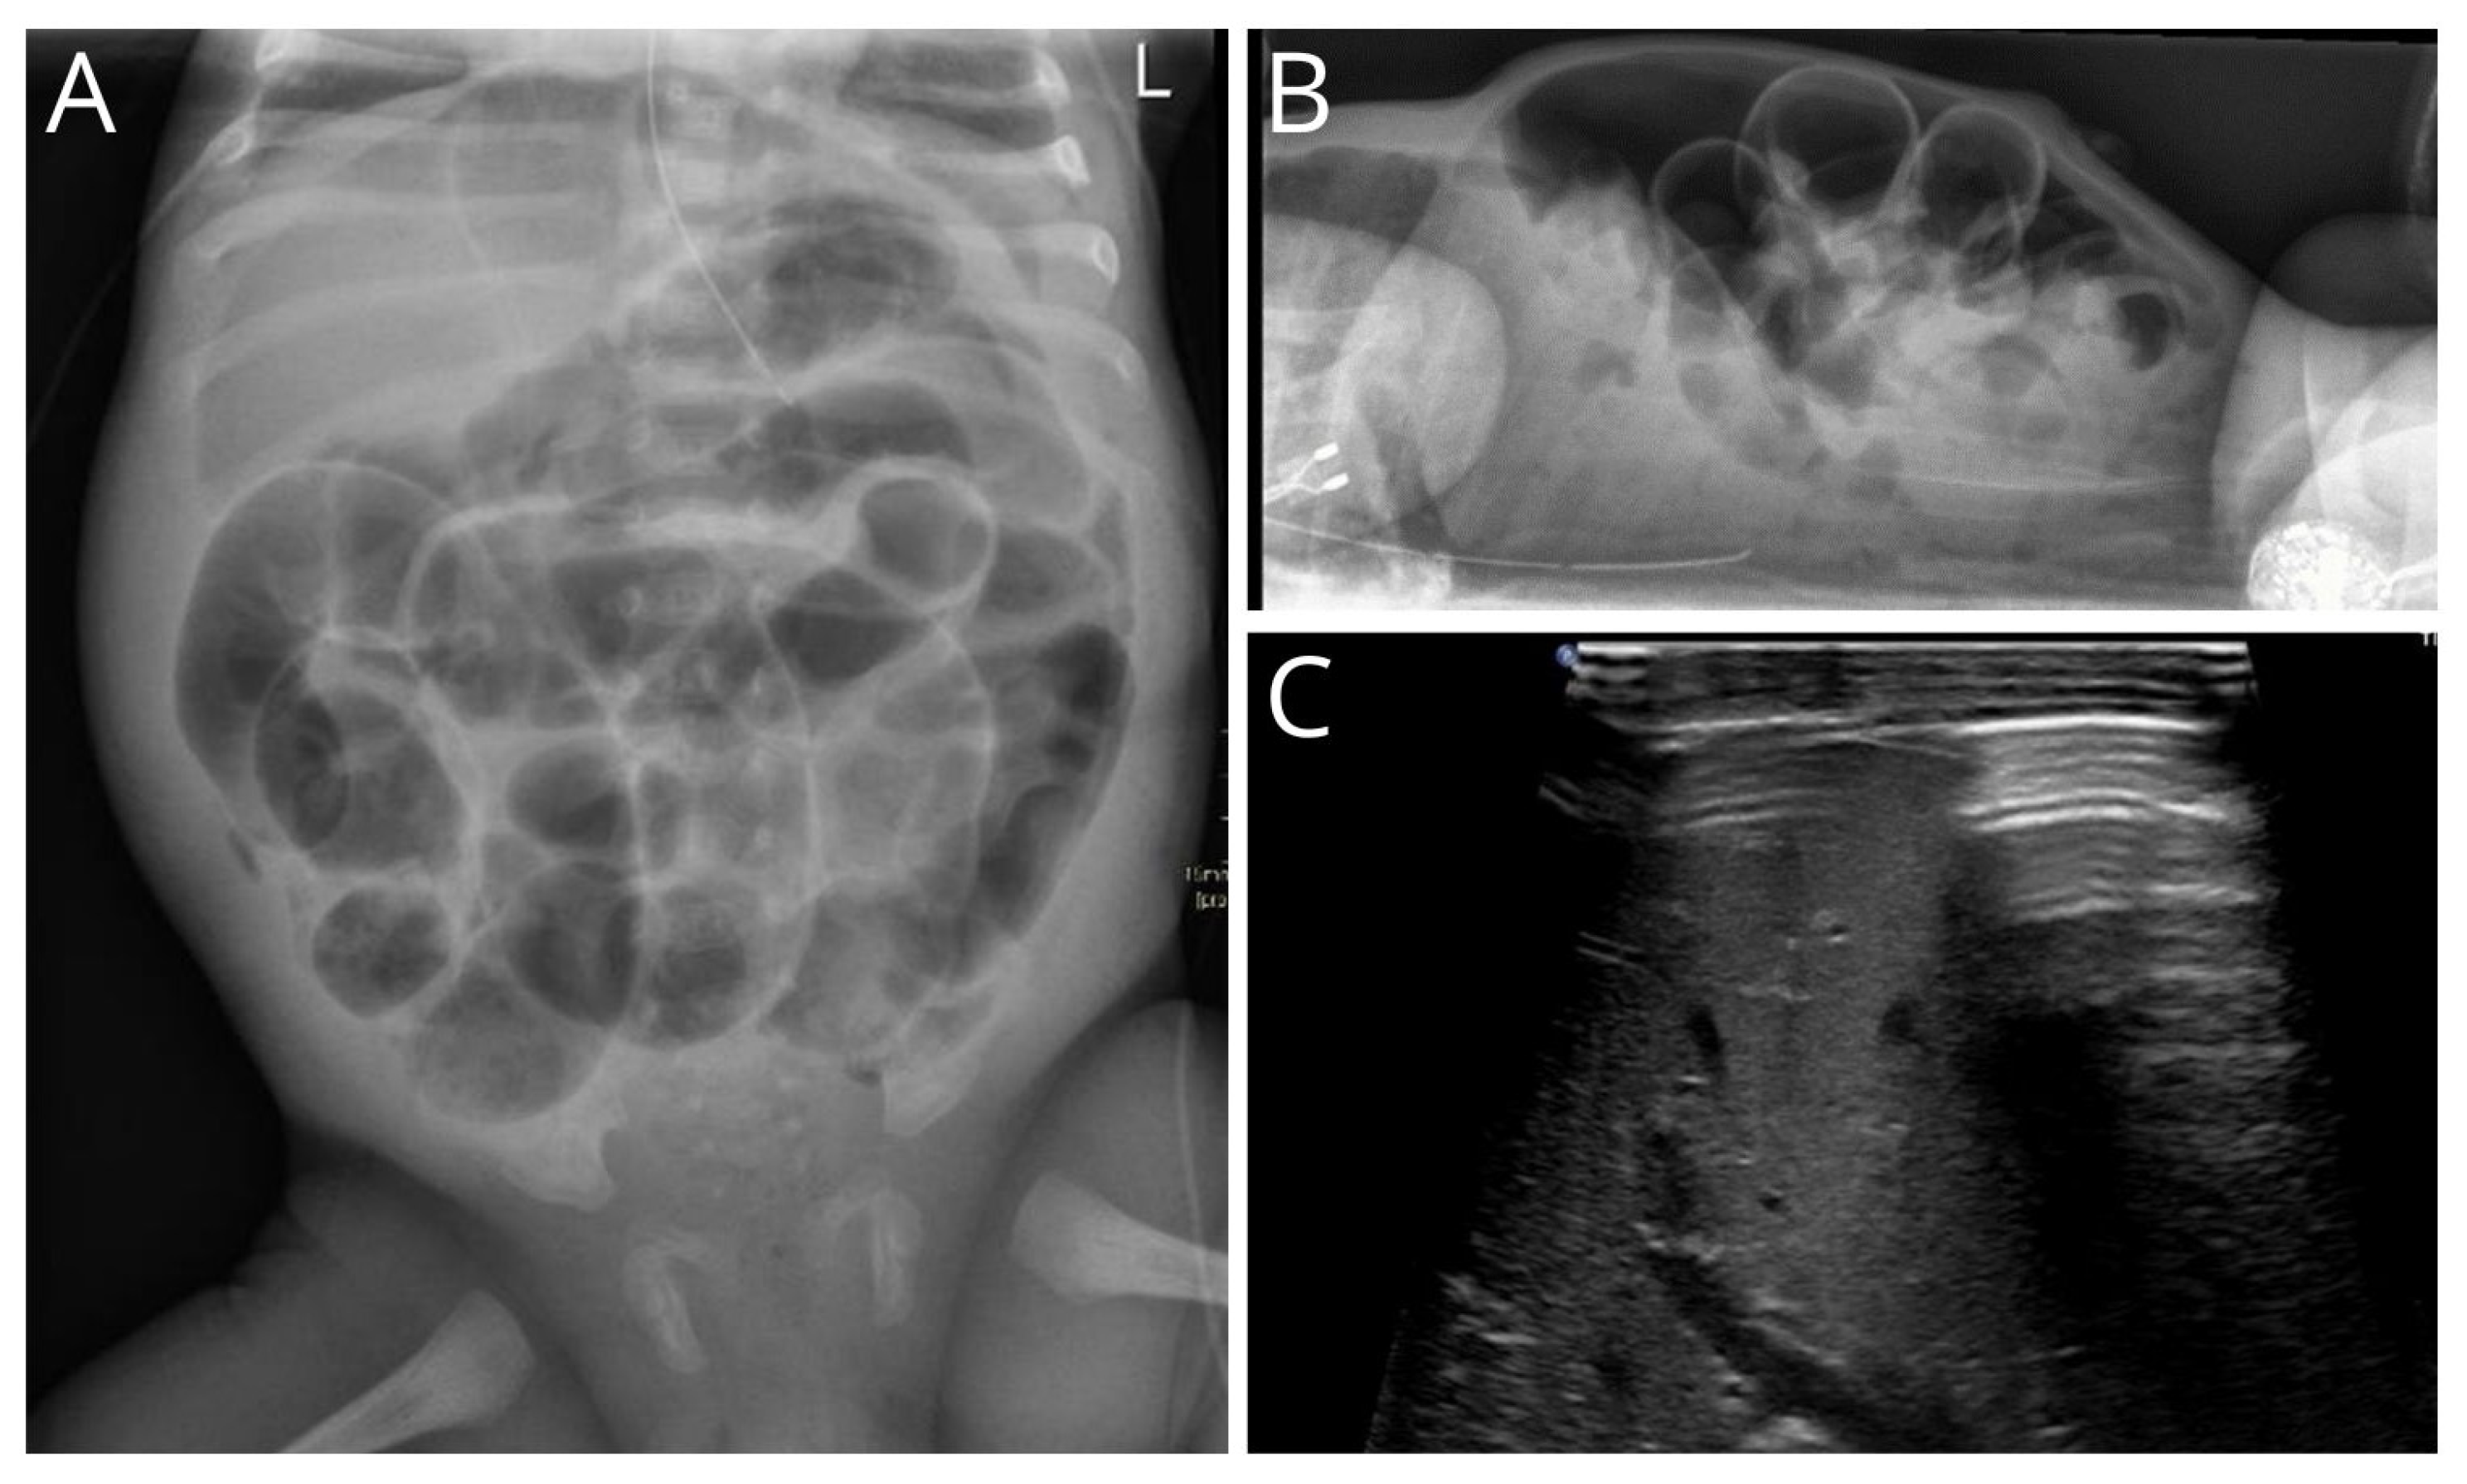

3.1. Radiological Findings

| Type of radiology | |

| X-ray | 45 (88.2) |

| Ultrasound | 5 (9.8) |

| Fistulogram | 1 (2.0) |

| Median age at radiological imaging in days (IQR) | 5 (3–9) |

| Amount of abdominal air | |

| Massive | 35 (74.5) |

| Locally | 9 (19.1) |

| Peel of air | 3 (6.4) |

| Dilated bowel | |

| None | 1 (2.1) |

| Some | 15 (31.9) |

| Multiple | 31 (66.0) |

| Pneumatosis intestinalis | 10 (21.3) |

| Ascites | 16 (34.0) |